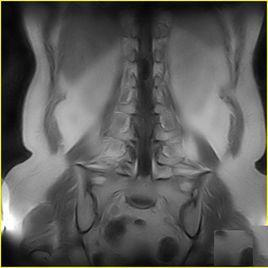

3、影像學檢查 頸部CT掃描除可了解腫瘤部位、範圍外,並有助於明確腫塊與頸動脈、頸內靜脈等重要結構的關係,為手術治療提供重要參考依據,但較小之腫塊,常不能顯影。為查找原發病灶,可酌情作鼻竇、鼻咽和喉側位等X線拍片檢查。對於頸部鰓裂瘺管或甲狀舌管瘺管,可行碘油造影X線拍片檢查,以了解瘺管走向和範圍。